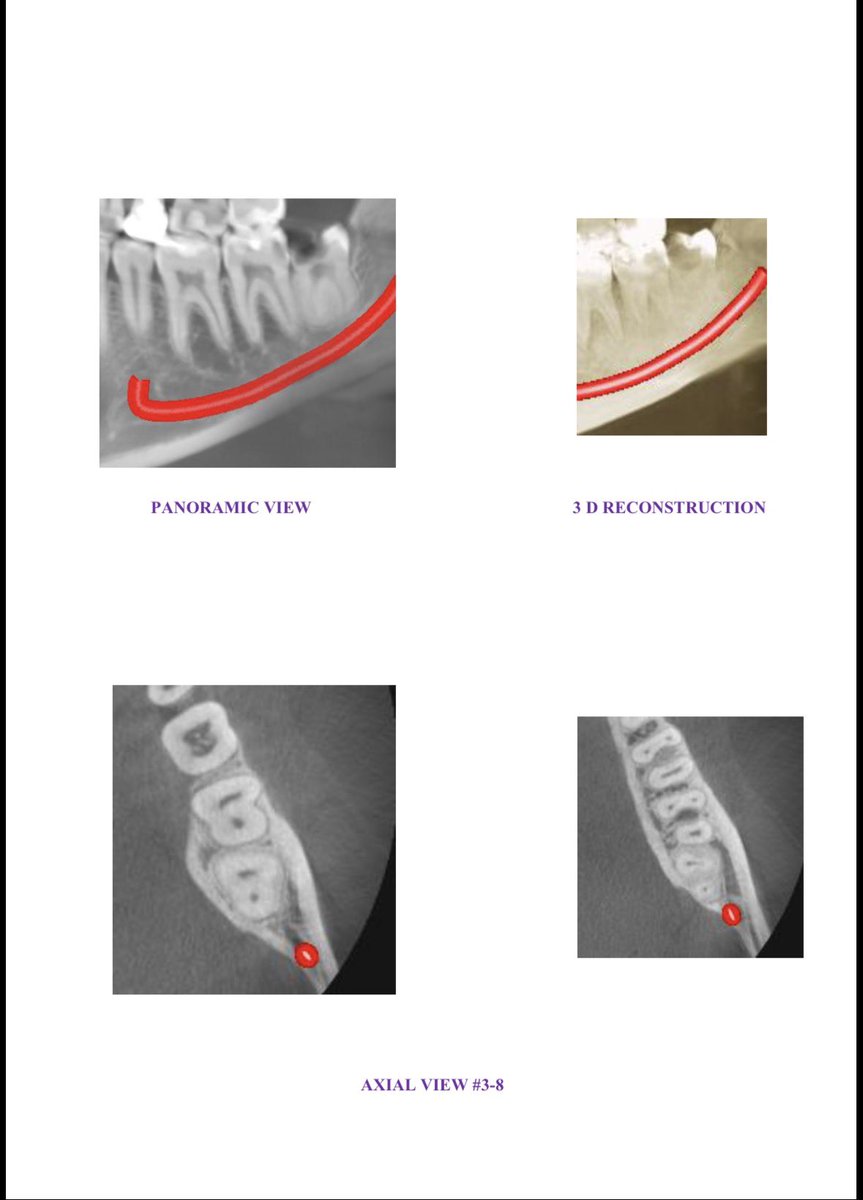

Got a CBCT scan done — basically a 3D X-ray of your jaw. Attaching it so you can see the chaos for yourself. Roots sideways. Teeth pressed into nerves. A red line tracing the inferior alveolar nerve, which if nicked means you lose feeling in half your face. Fun.

The surgeon studied it like a mechanic studying a car that’s been “running fine” for years. “Should’ve done this earlier.” Doctor-speak for “you’re an idiot.”